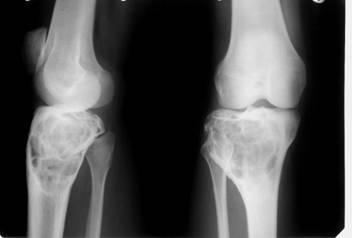

a)     Mielomul multiplu (plasmocitomul) – poate afecta toate segmentele scheletice realizand demineralizare difuza si multiple imagini osteolitice rotunde, omogene, bine delimitate, fara reactie periostala. Confluarea acestor lacune poate merge pana la stergerea unui segment osos. Fracturile spontane sunt prezente.

Fig. 90 – Mielom multiplu